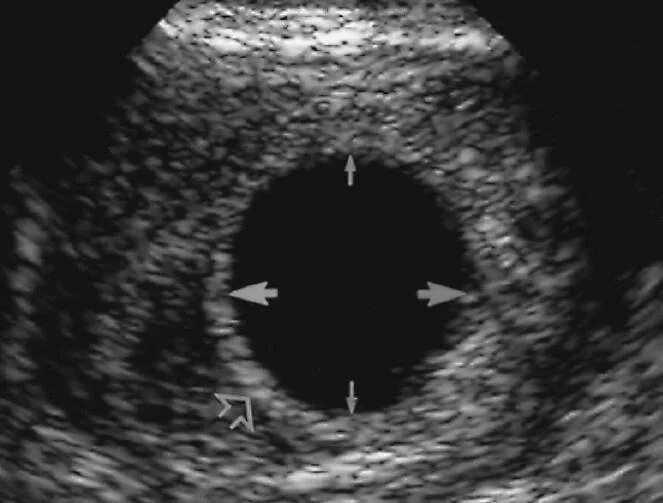

Плодном яйце не визуализируется эмбрион